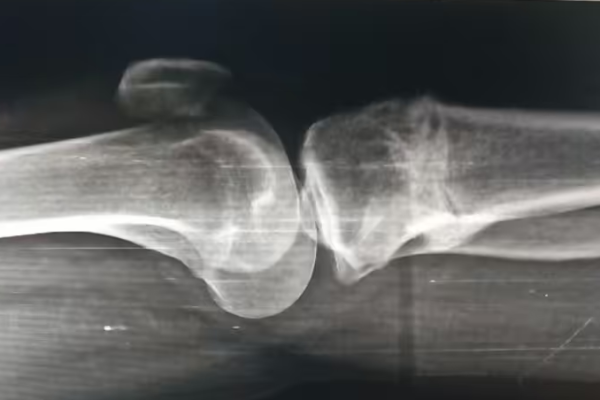

Новый материал представляет собой композитные гранулы из полилактида и гидроксиапатита. Особенная полимерная оболочка сохраняет форму гранул и создаёт прочную основу для роста кровеносных сосудов и костной ткани.